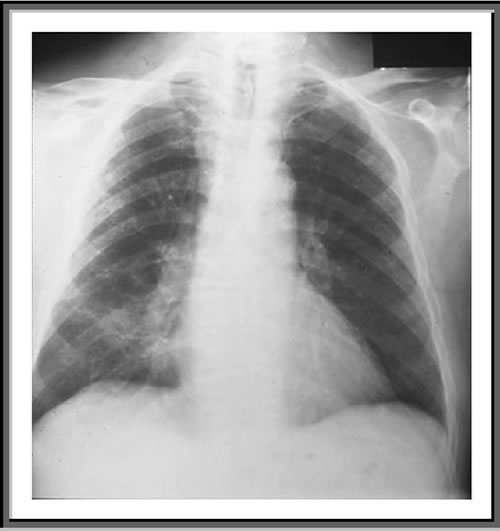

un aspetto caratteristico dell'RX torace?

Inizialmente

L'RX può essere normale. In seguito possono comparire

infiltrati interstiziali peri-ilari, con progressione verso la

periferia. Il quadro può progredire con consolidamento degli

spazi aerei (alveolari) bilaterali, mimando un edema polmonare, ma

con risparmio degli spazi costo-frenici e degli apici

Un 20%

dei soggetti presentano quadri atipici, che includono formazioni di

pneumatoceli, infiltrati monolaterali e/o lobari,

noduli,linfoadenopatia mediastinica e versamenti pleurici.

In

seguito al trattamento l'Rx può rimanere inalterato per 7-10

gg. In alcuni casi anche dopo completa guarigione ed in assenza di

sintomi persistono anomalie radiologiche. In altri casi residuano

fibrosi e/o bronchiectasie post-infettive.

Rx

torace di un paziente con PCP: infiltrati misti interstiziali ed

alveolari, più evidenti all'emitorace di destra.